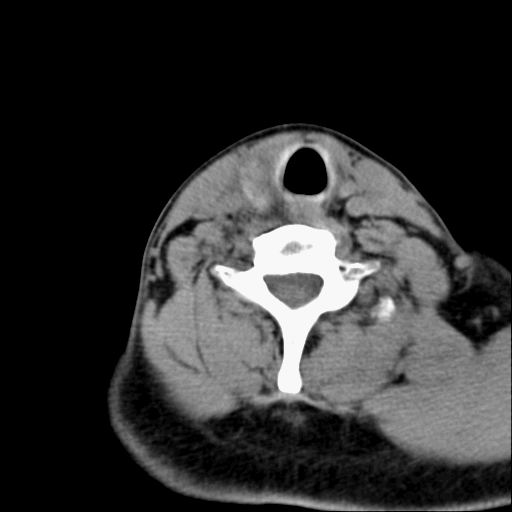

标题: CT23947 右颈部触及00.5x1.5cm质硬长形肿块,疼痛 [打印本页]

标题: CT23947 右颈部触及00.5x1.5cm质硬长形肿块,疼痛

右侧甲状腺腺瘤考虑

甲状腺癌可疑

右侧甲状腺病灶,建议增强或结合b超检查。

右甲状腺占位,建议增强。

甲状腺腺瘤或癌

甲状腺腺瘤或癌.

甲状腺右叶占位病变,建议增强扫描。

甲状腺占位  定性有时很难 但无论癌还是腺瘤 还是手术比较好!以下是甲状腺占位的ct鉴别诊断

ct对甲状腺病变的诊断作用

确定病变范围,判断有无部属淋巴腺转移,甲状腺肿物没有可靠的征象鉴别良、恶性,如有部属淋巴结肿大、喉返神经麻痹、甲状软骨或其它喉软骨破坏等表现,则有利于诊断恶性。钙化不是鉴别良、恶性的依据。

1.甲状腺ca:中年妇女好发,病例分型,乳头状、滤泡状、未分化癌及髓样癌四种。

ct表现:形态不规则的软组织密度肿块,可累及部分或大部分甲状腺组织,密度不均,可坏死、囊变、钙化,增强病灶呈不均匀强化,有局部侵犯或转移时可有颈部淋巴结肿大。

2.甲状腺腺瘤;常见的良性肿瘤,病理分型:滤泡状腺瘤、乳头状囊性腺瘤,以前者多见,腺瘤周围有完整的包膜,患者大多为中青年女性,大部分无任何临床症状。

ct表现肿瘤呈稍低密度结节状肿块,边缘光整、锐利病灶均匀强化,少数腺瘤可有钙化。

3.甲状腺肿:分结节性和弥漫性甲状腺肿。前者根据有无甲亢症状分为毒性和非毒性;后者包括桥本甲状腺炎和突眼性甲状腺肿,均属自身免疫性疾病。病理上桥本甲状腺炎可见甲状腺组织被大量淋巴细胞侵润,并形成淋巴滤泡,而突眼性甲状腺肿以滤泡增生为主要特征。

ct表现:甲状腺弥漫性增大,边缘清楚,密度均匀或不甚均匀,增强扫描有强化。结节状甲状腺肿尚可见在增大的甲状腺组织内有多发结节状低密度或高密度区,并常多发性钙化。

甲状腺腺瘤或癌,结合增强或彩超

甲状腺右侧叶占位,定性困难,建议增强。

右侧甲状腺低密度病灶,性质待定;建议行进一步检查。